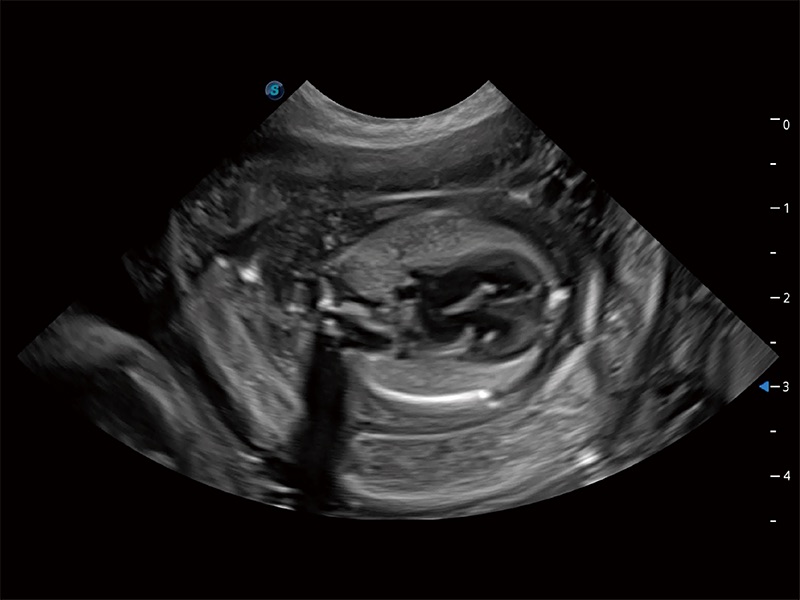

优异的基础图像

ProPet 80 全新的动物超声智能软件和丰富的探头群,为动物医生提供了高清晰度和精细分辨率的图像,无论在宠物、马科、畜牧还是实验室动物等应用中都可以轻松应对,为您的日常工作带来满意的体验。

(犬)胎儿主动脉弓立体血流

(犬)胎儿四腔心